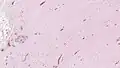

Micrograph of an aggressive angiomyxoma. Core biopsy. H&E stain.

Microscopy

• Vascular appearance of tumor[7]

• Hypocellular mesenchymal lesion

• Spindled and stellate cells with an ill-defined cytoplasm

• Cells loosely scattered in a myxoid stroma

• No evidence of nuclear atypia and mitosis

• Numerous, thin-to-thick wall vessels of different sizes

• Myxoid, hypocellular background

• Bland cytological appearance of spindle cells